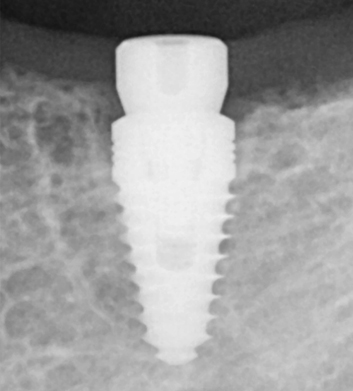

A dental implant is a prosthetic tooth, usually made of titanium, designed to replace your tooth after it has been lost or extracted. Implants are designed to replace both the root and crown of your teeth to give you a solution that looks feels and functions just like your original tooth. Dental Implants consist of three main parts, the implant screw which is implanted into the bone, the abutment which supports the final restoration and the zirconium implant restoration.

Dental implants, surgically inserted into the jawbone, act as artificial tooth roots for anchoring prosthetics, offering a lasting solution for tooth loss. The dental implant abutment is usually attached to the implant body with abutment screw and extends through gums into mouth to support the attached artificial teeth.